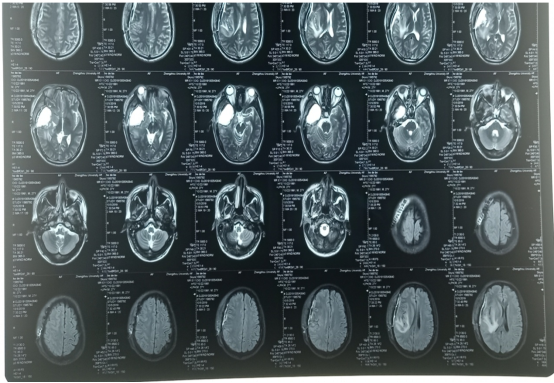

20200220三门峡黄河医院:右侧颞叶胶质瘤术后,右侧局部脑膜增厚,术区未见明显异常强化。

20200512三门峡市中心医院:右颞部胶质瘤术后改变,硬膜下积液。